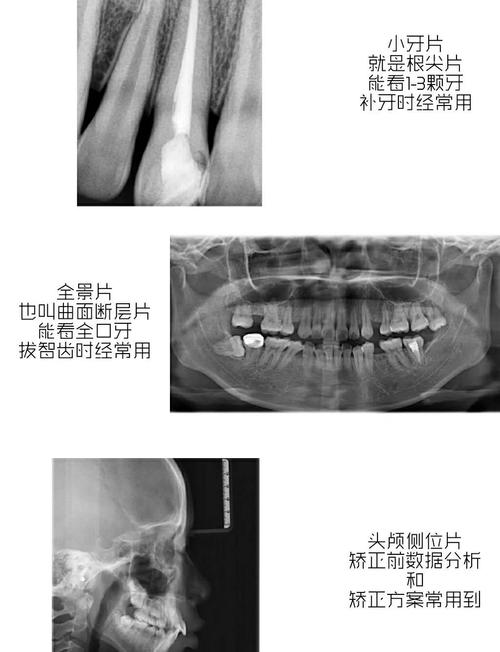

Q1:牙片CT和普通牙片(根尖片、曲面断层片)有什么区别?

A:牙片CT是三维影像,可多角度、多层面显示颌骨内部结构(如下颌神经管、根尖病变三维范围),分辨率高(可达0.1mm),尤其适用于复杂病例(如种植术前评估、根管治疗疑难根管);普通牙片是二维影像,存在结构重叠(如上颌窦与牙根重叠),分辨率较低,但辐射剂量更小,价格更低,适用于常规检查。